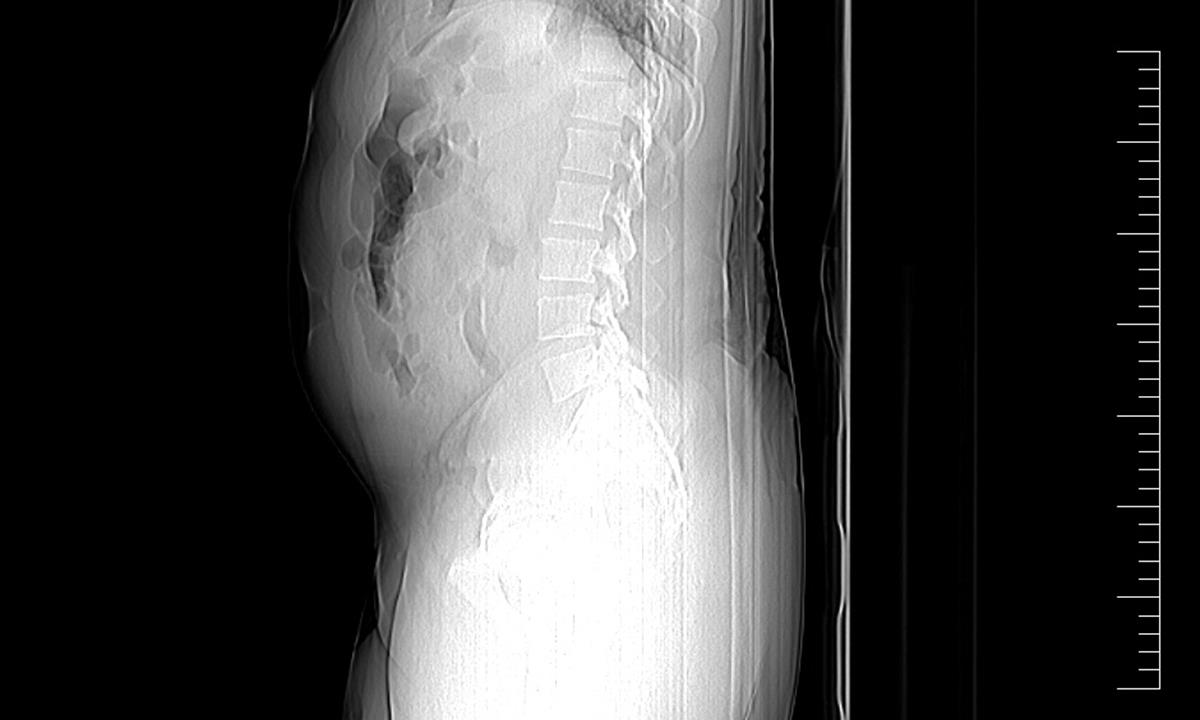

Minulý týden opět celníci na letišti Václava Havla v Praze Ruzyni odhalili pašeráka – polykače. Tentokrát se jednalo o 39letého nigerijského státního příslušníka, který postupně vyloučil 19 kapslí obsahujících drogy. Cizinec cestoval na pravidelné lince Madrid-Praha.

Ke kontrole byl polykač celníky vytipován na základě provedené rizikové analýzy daného letu. Prvotní podezření na pašování drog celníkům potvrdily kontrolní stěry z rukou pašeráka.

Postupně z těla pašeráka vyšlo všech 19 kontejnerků naplněných bílým práškem. Chemická látka při provedení detekční zkoušky pozitivně reagovala jako kokain. Celková hmotnost všech kapslí včetně drogy je 211,4 gramů. Určení vlastní hmotnosti a druhu zajištěné drogy je předmětem další odborné expertízy. Podle zkušeností celníků se s největší pravděpodobností jedná o velmi koncentrovaný kokain. Zda byla droga určena na český trh nebo k distribuci v jiné zemi, je předmětem dalšího šetření.